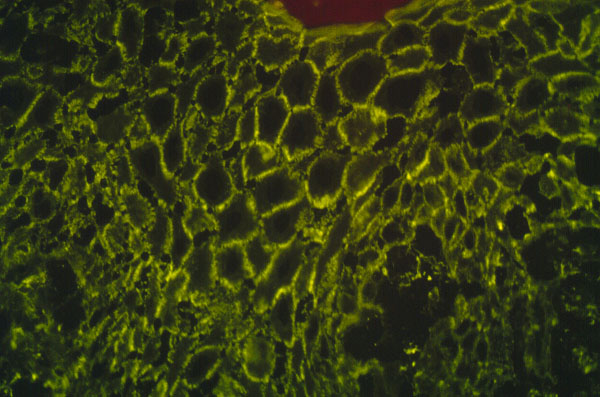

Pemphigus vulgaris

, micro, immunofluorescence stained for IgG, detected antibody is against epidermal cell surface.